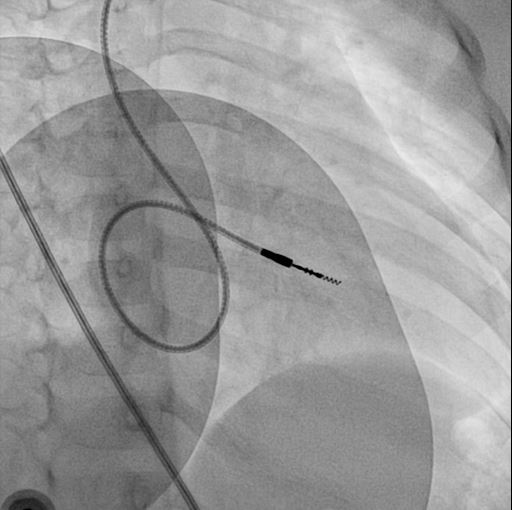

screw.jpg

RVOT pacing

screwe.jpg